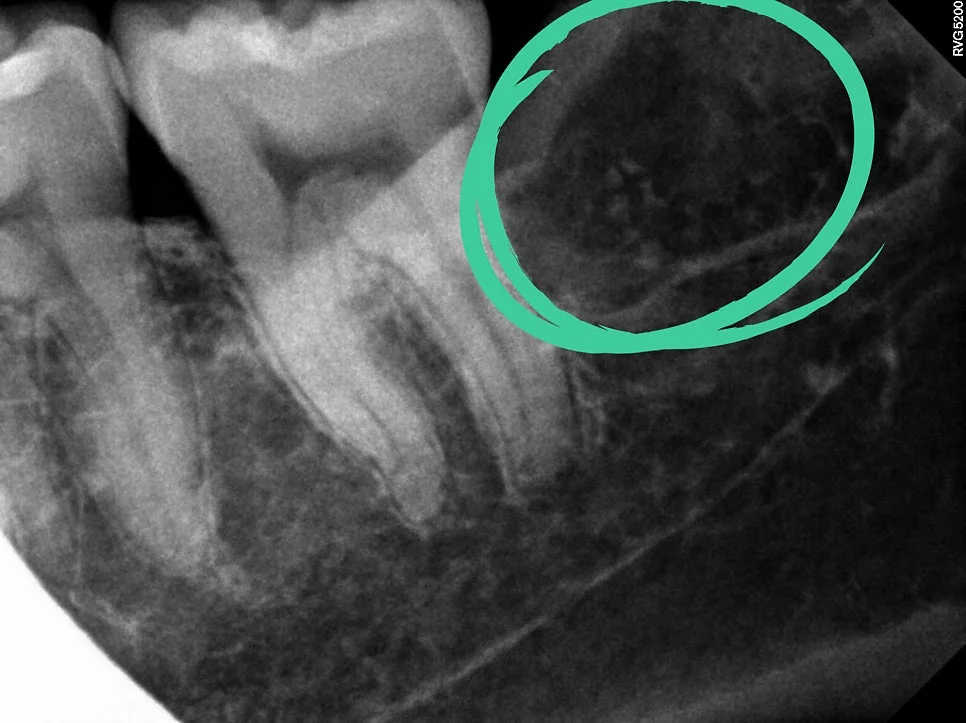

오른쪽 사랑니 확대 — 오렌지색 화살표(신경관), 파란색 화살표(휜 뿌리)

오른쪽 사랑니는 겉으로 보기엔 단순해 보였지만, 뿌리 끝이 심하게 휘어 있고 신경관과 맞닿아 있었습니다.

이런 경우에는 치아가 한 번에 안 나오니까, 머리와 뿌리를 나눠서 발치해야 합니다. 난도가 높은 편이라 보통 15~20분 정도 걸리는데, 단계별로 차근차근 발치를 해주면 됩니다.